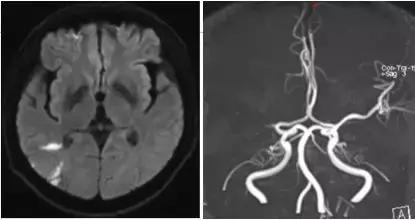

磁共振提示脑梗死,右侧大脑中动脉闭塞

磁共振提示大面积脑缺血,存在可挽救的脑组织